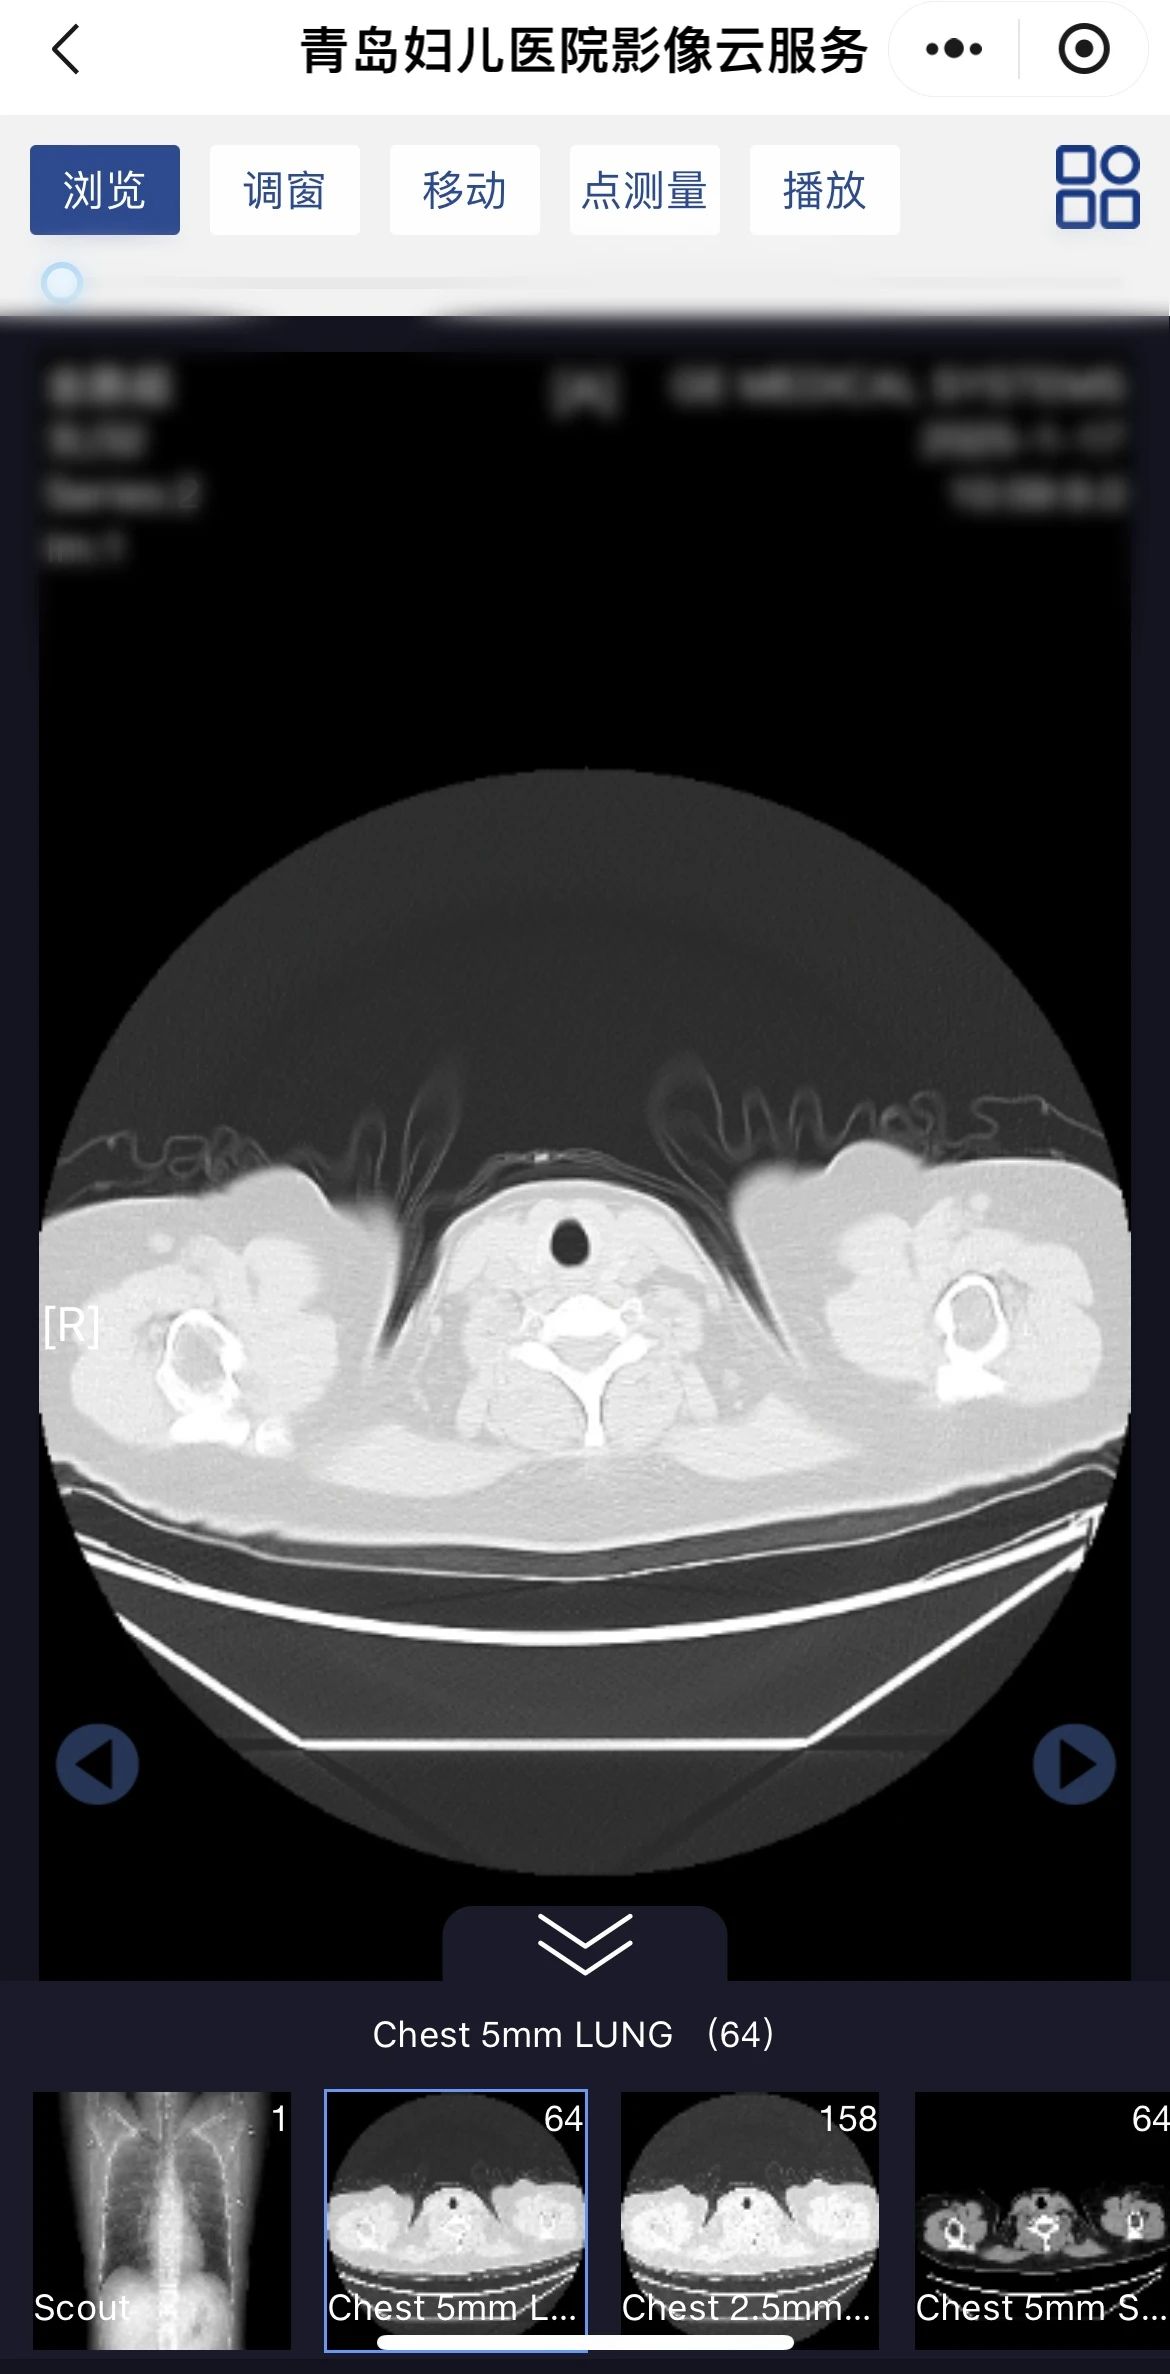

“云膠片”中的影像圖像更加完整,能夠查看DICOM原始影像,并具備縮放、移動(dòng)、動(dòng)態(tài)展示等多種圖片處理功能,方便醫(yī)生診斷分析。

點(diǎn)擊“醫(yī)學(xué)影像平臺(tái)”,進(jìn)入“青島婦兒醫(yī)院影像云”。